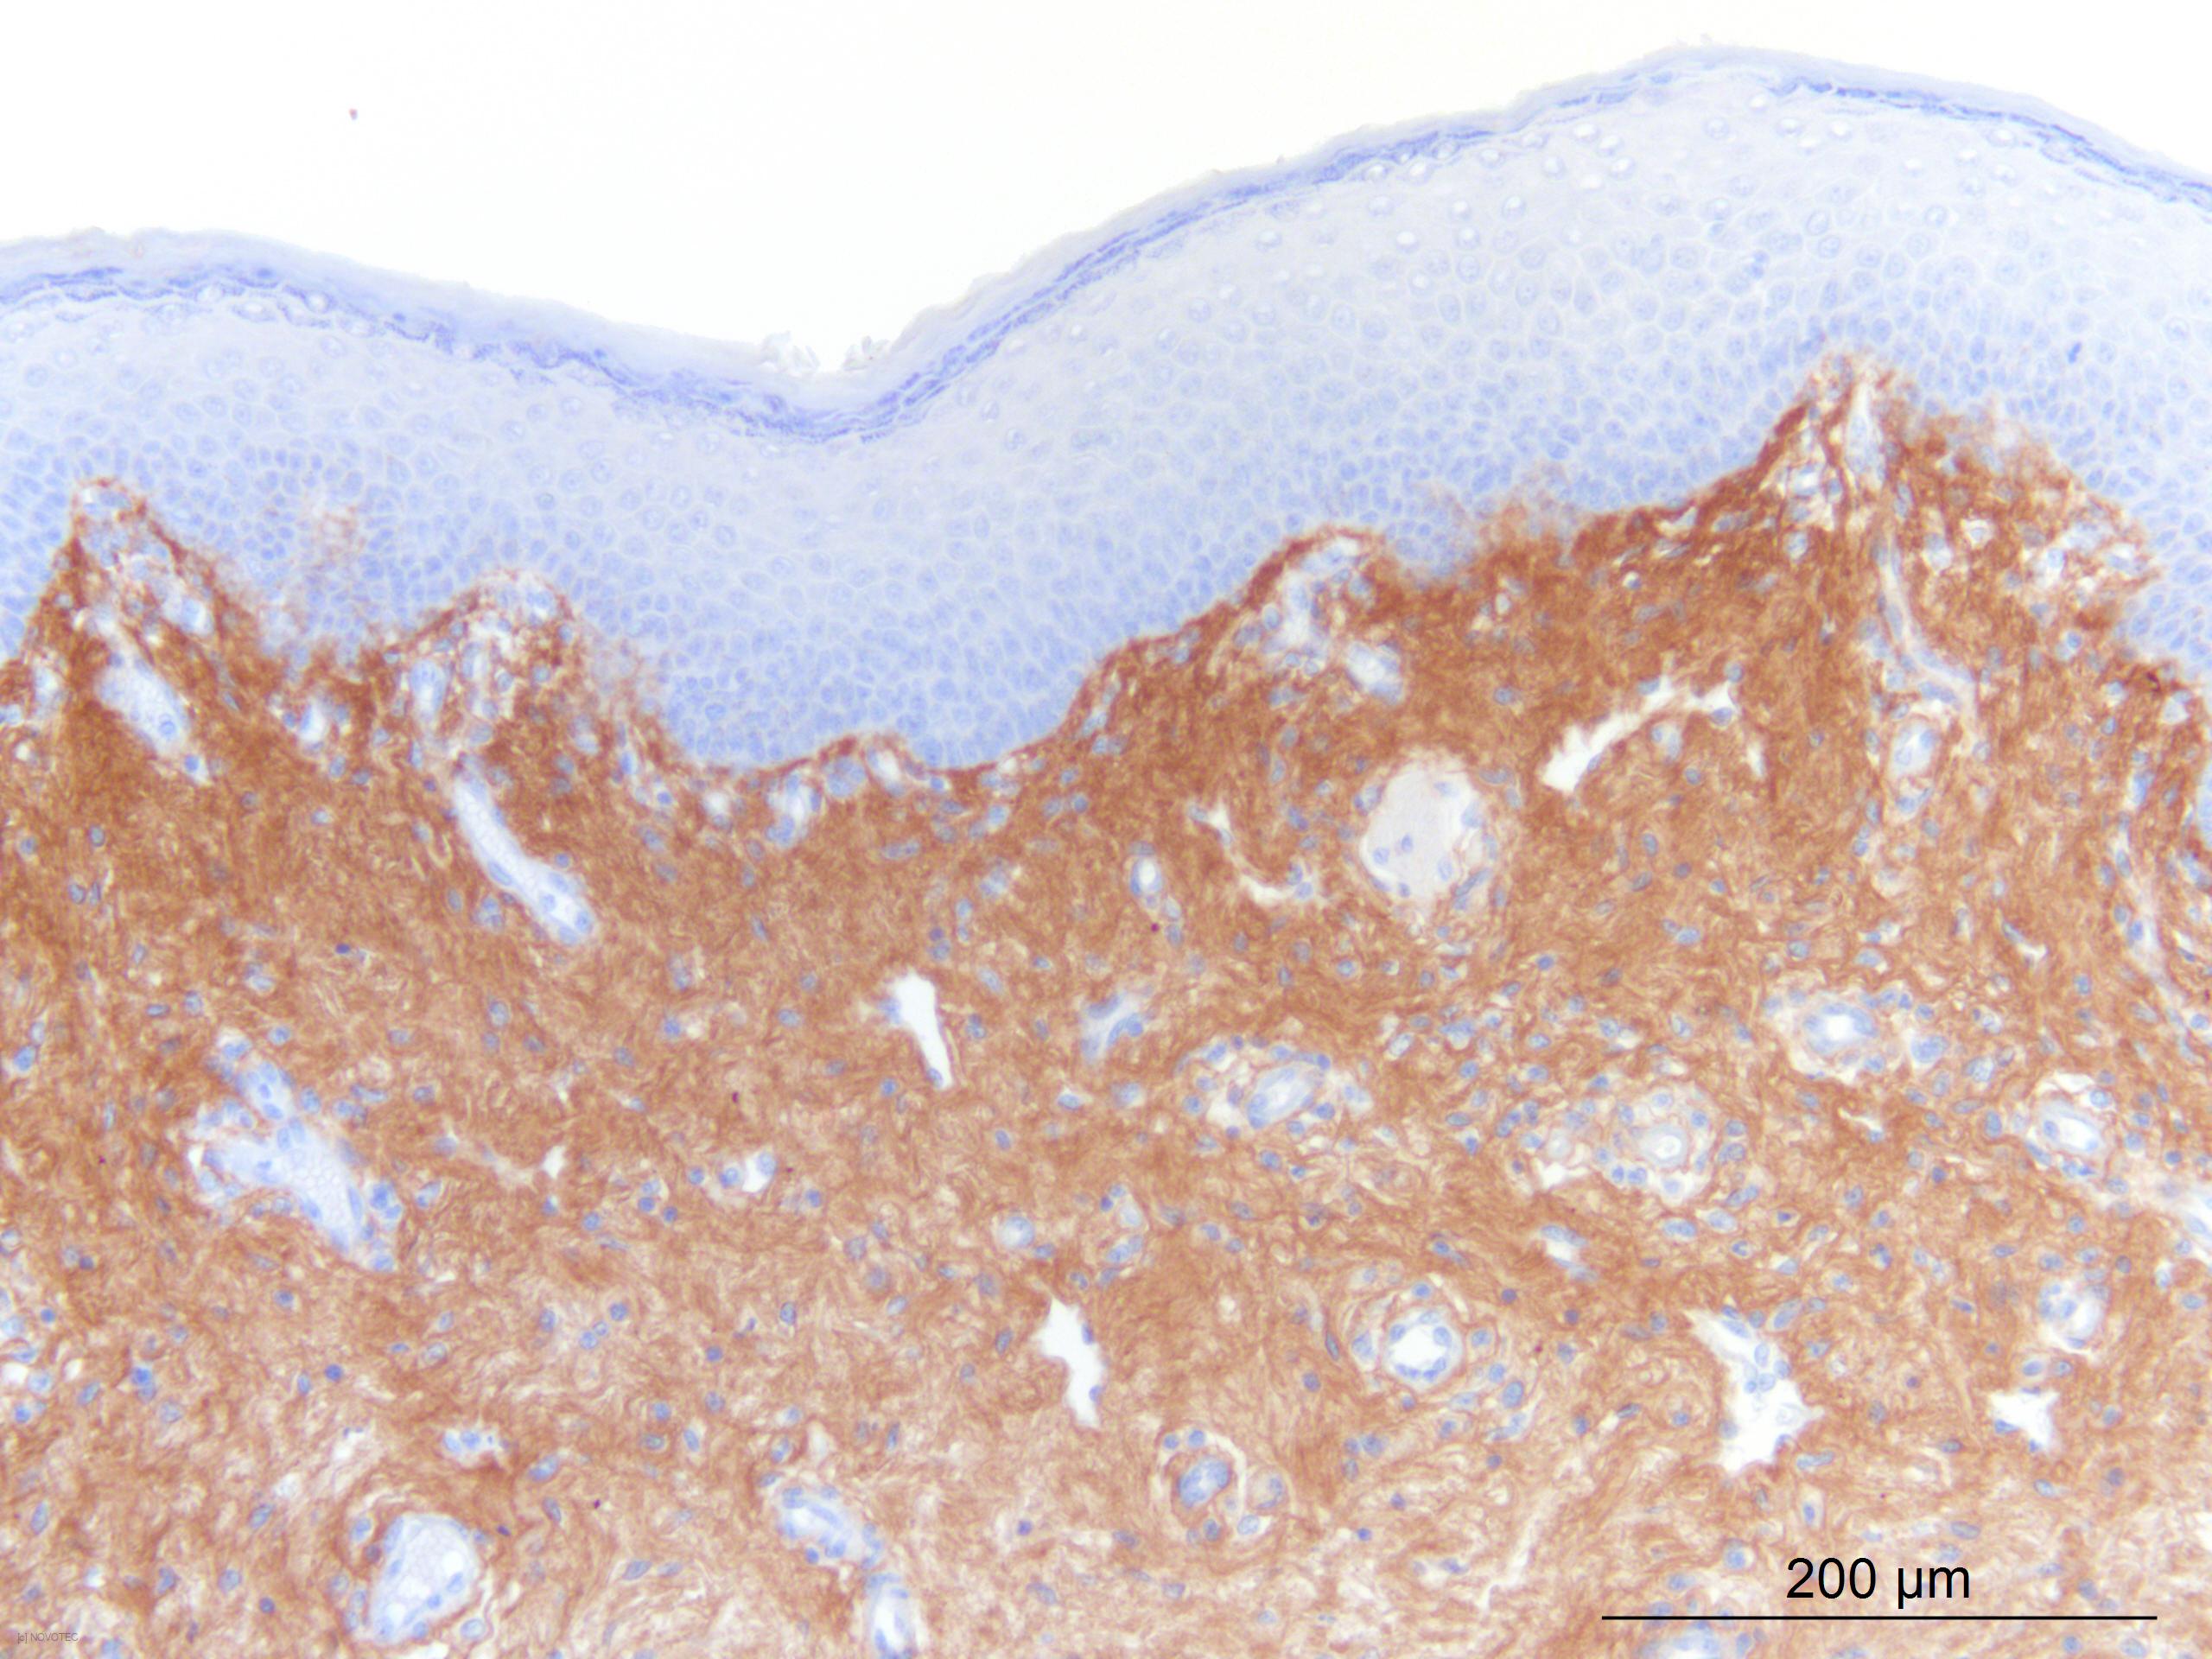

Immunoperoxidase technique with the Envision / Dako kit, hyaluronidase 0.5% pretreatment, optimal working dilution at 1/500 on fixed paraffin-embedded human skin.

Immunoperoxidase technique with the Envision / Dako kit, 0.5% hyaluronidase pretreatment, optimal working dilution at 1/500 on fixed paraffin-embedded human skin.